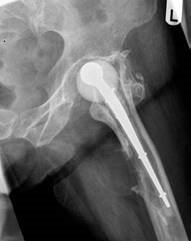

EXAMINER: Here is a lateral radiograph of the left hip that was taken on admission. (Figure 2.2.)

Figure 2.2 Lateral radiograph of loose left cemented Thompsonโs hemiarthroplasty hip.

CANDIDATE: The lateral radiograph demonstrates loosening of the Thompsonโs prosthesis with a large cortical lytic lesion surrounding the stem. There appears be reactive bone formation along the posteromedial diaphysis of the femur and a suggestion of a possible soft tissue mass. There is lateral cortical destruction at the tip of the stem.